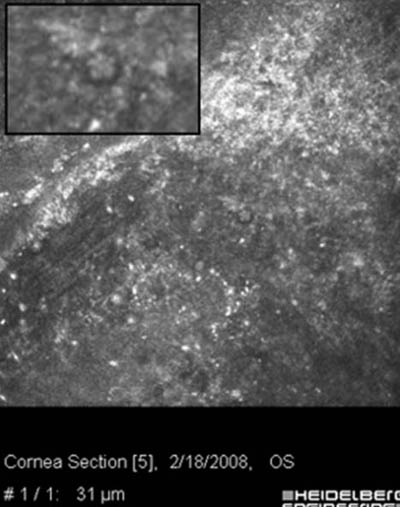

- Microscopia Confocal : 94 a 100% de especificidad y 80 a 84% de sensibilidad

Microscopía Confocal